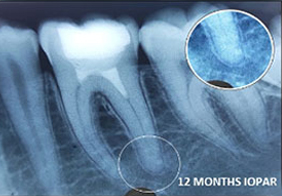

Amanulla -

PRF Mediated REP in 22 with 18 months Follow up

Complete Bony Healing, Calcific Bridge Formed.

PRF Mediated REP in 21 with 26 Months Follow Up

Complete Bony Healing, Apex Closed, Lateral Dentinal Wall Thickened, PDL Apically